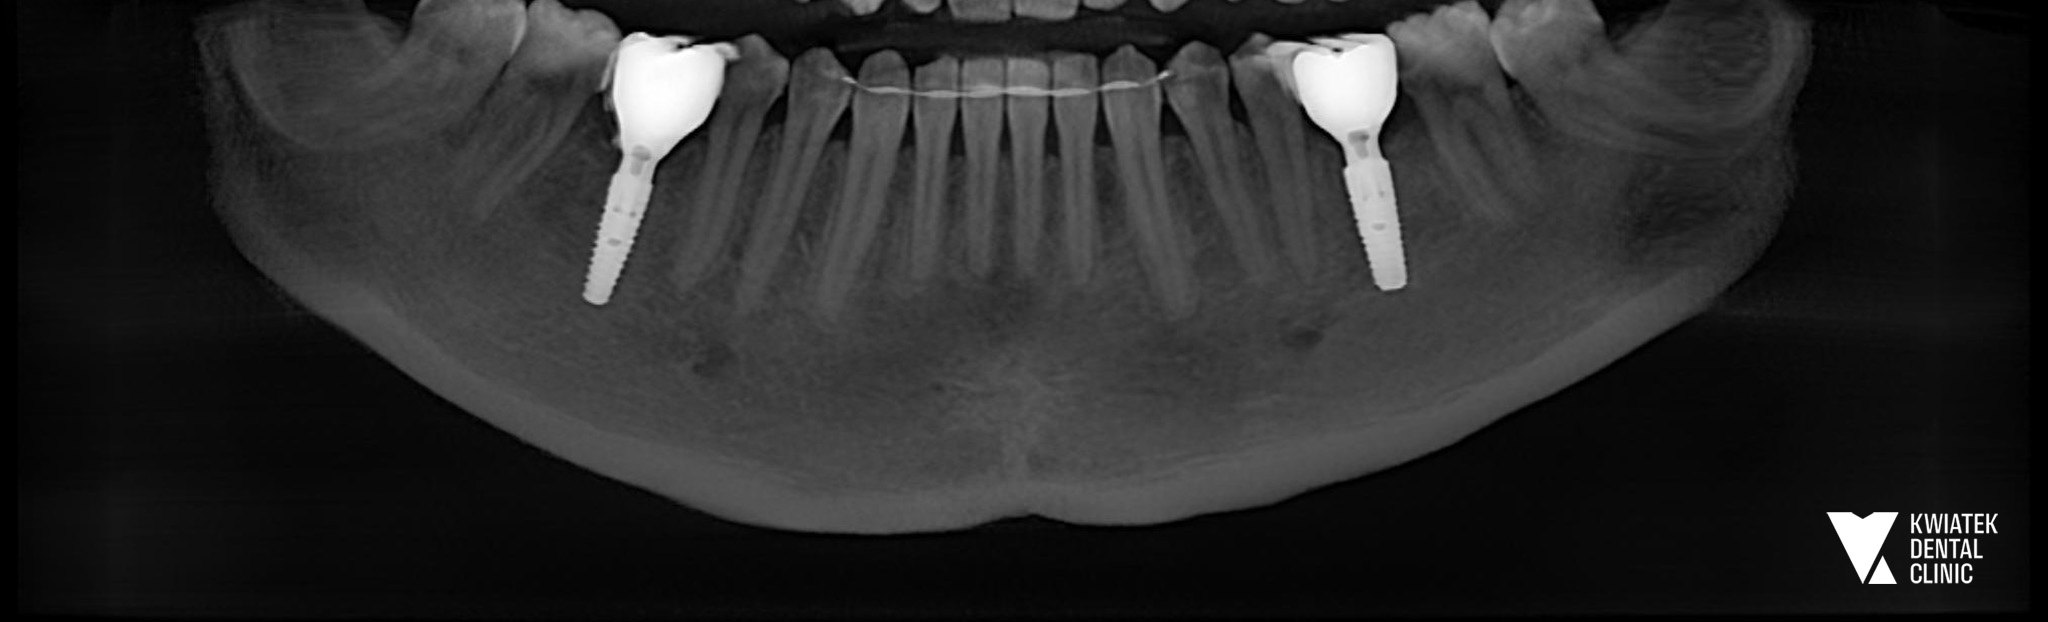

PO

Na podstawie diagnostyki stwierdzono brak zębów 36 oraz 46 w żuchwie. Już wcześniej, podczas wcześniejszych wizyt, zaproponowano Pacjentce odbudowę tych braków przy użyciu implantów, jako najbardziej przewidywalnej i trwałej metody leczenia.

Zabieg implantologiczny został przeprowadzony zgodnie z wcześniej przygotowanym planem. W trakcie procedury zastosowano nowoczesny system implantologiczny MIS C1. W pierwszym etapie wykonano augmentację kości z wykorzystaniem materiału kościozastępczego Bio-Oss oraz kości własnej Pacjentki, co pozwoliło na optymalne przygotowanie podłoża kostnego pod implanty. Następnie wszczepiono dwa implanty w znieczuleniu miejscowym przy użyciu szablonu chirurgicznego, co zapewniło maksymalną precyzję pozycjonowania implantów. W trakcie zabiegu wykonano również śródzabiegową kontrolę radiologiczną RVG oraz badanie CBCT żuchwy. W tym przypadku po implantacji założono śruby gojące, a tkanki miękkie zabezpieczono szwami chirurgicznymi. Pacjentce przekazano szczegółowe zalecenia pozabiegowe oraz wdrożono odpowiednie leczenie farmakologiczne.

Po okresie osteointegracji przeprowadzono etap protetyczny. Wykonano cyfrowe skanowanie implantów z wykorzystaniem scanpostów oraz dobrano odpowiednie łączniki protetyczne typu Ti-base. Finalnym etapem leczenia było wykonanie i osadzenie pełnoceramicznych koron na implantach w miejscach zębów 36 oraz 46, które zostały precyzyjnie dokręcone i zabezpieczone materiałem kompozytowym.